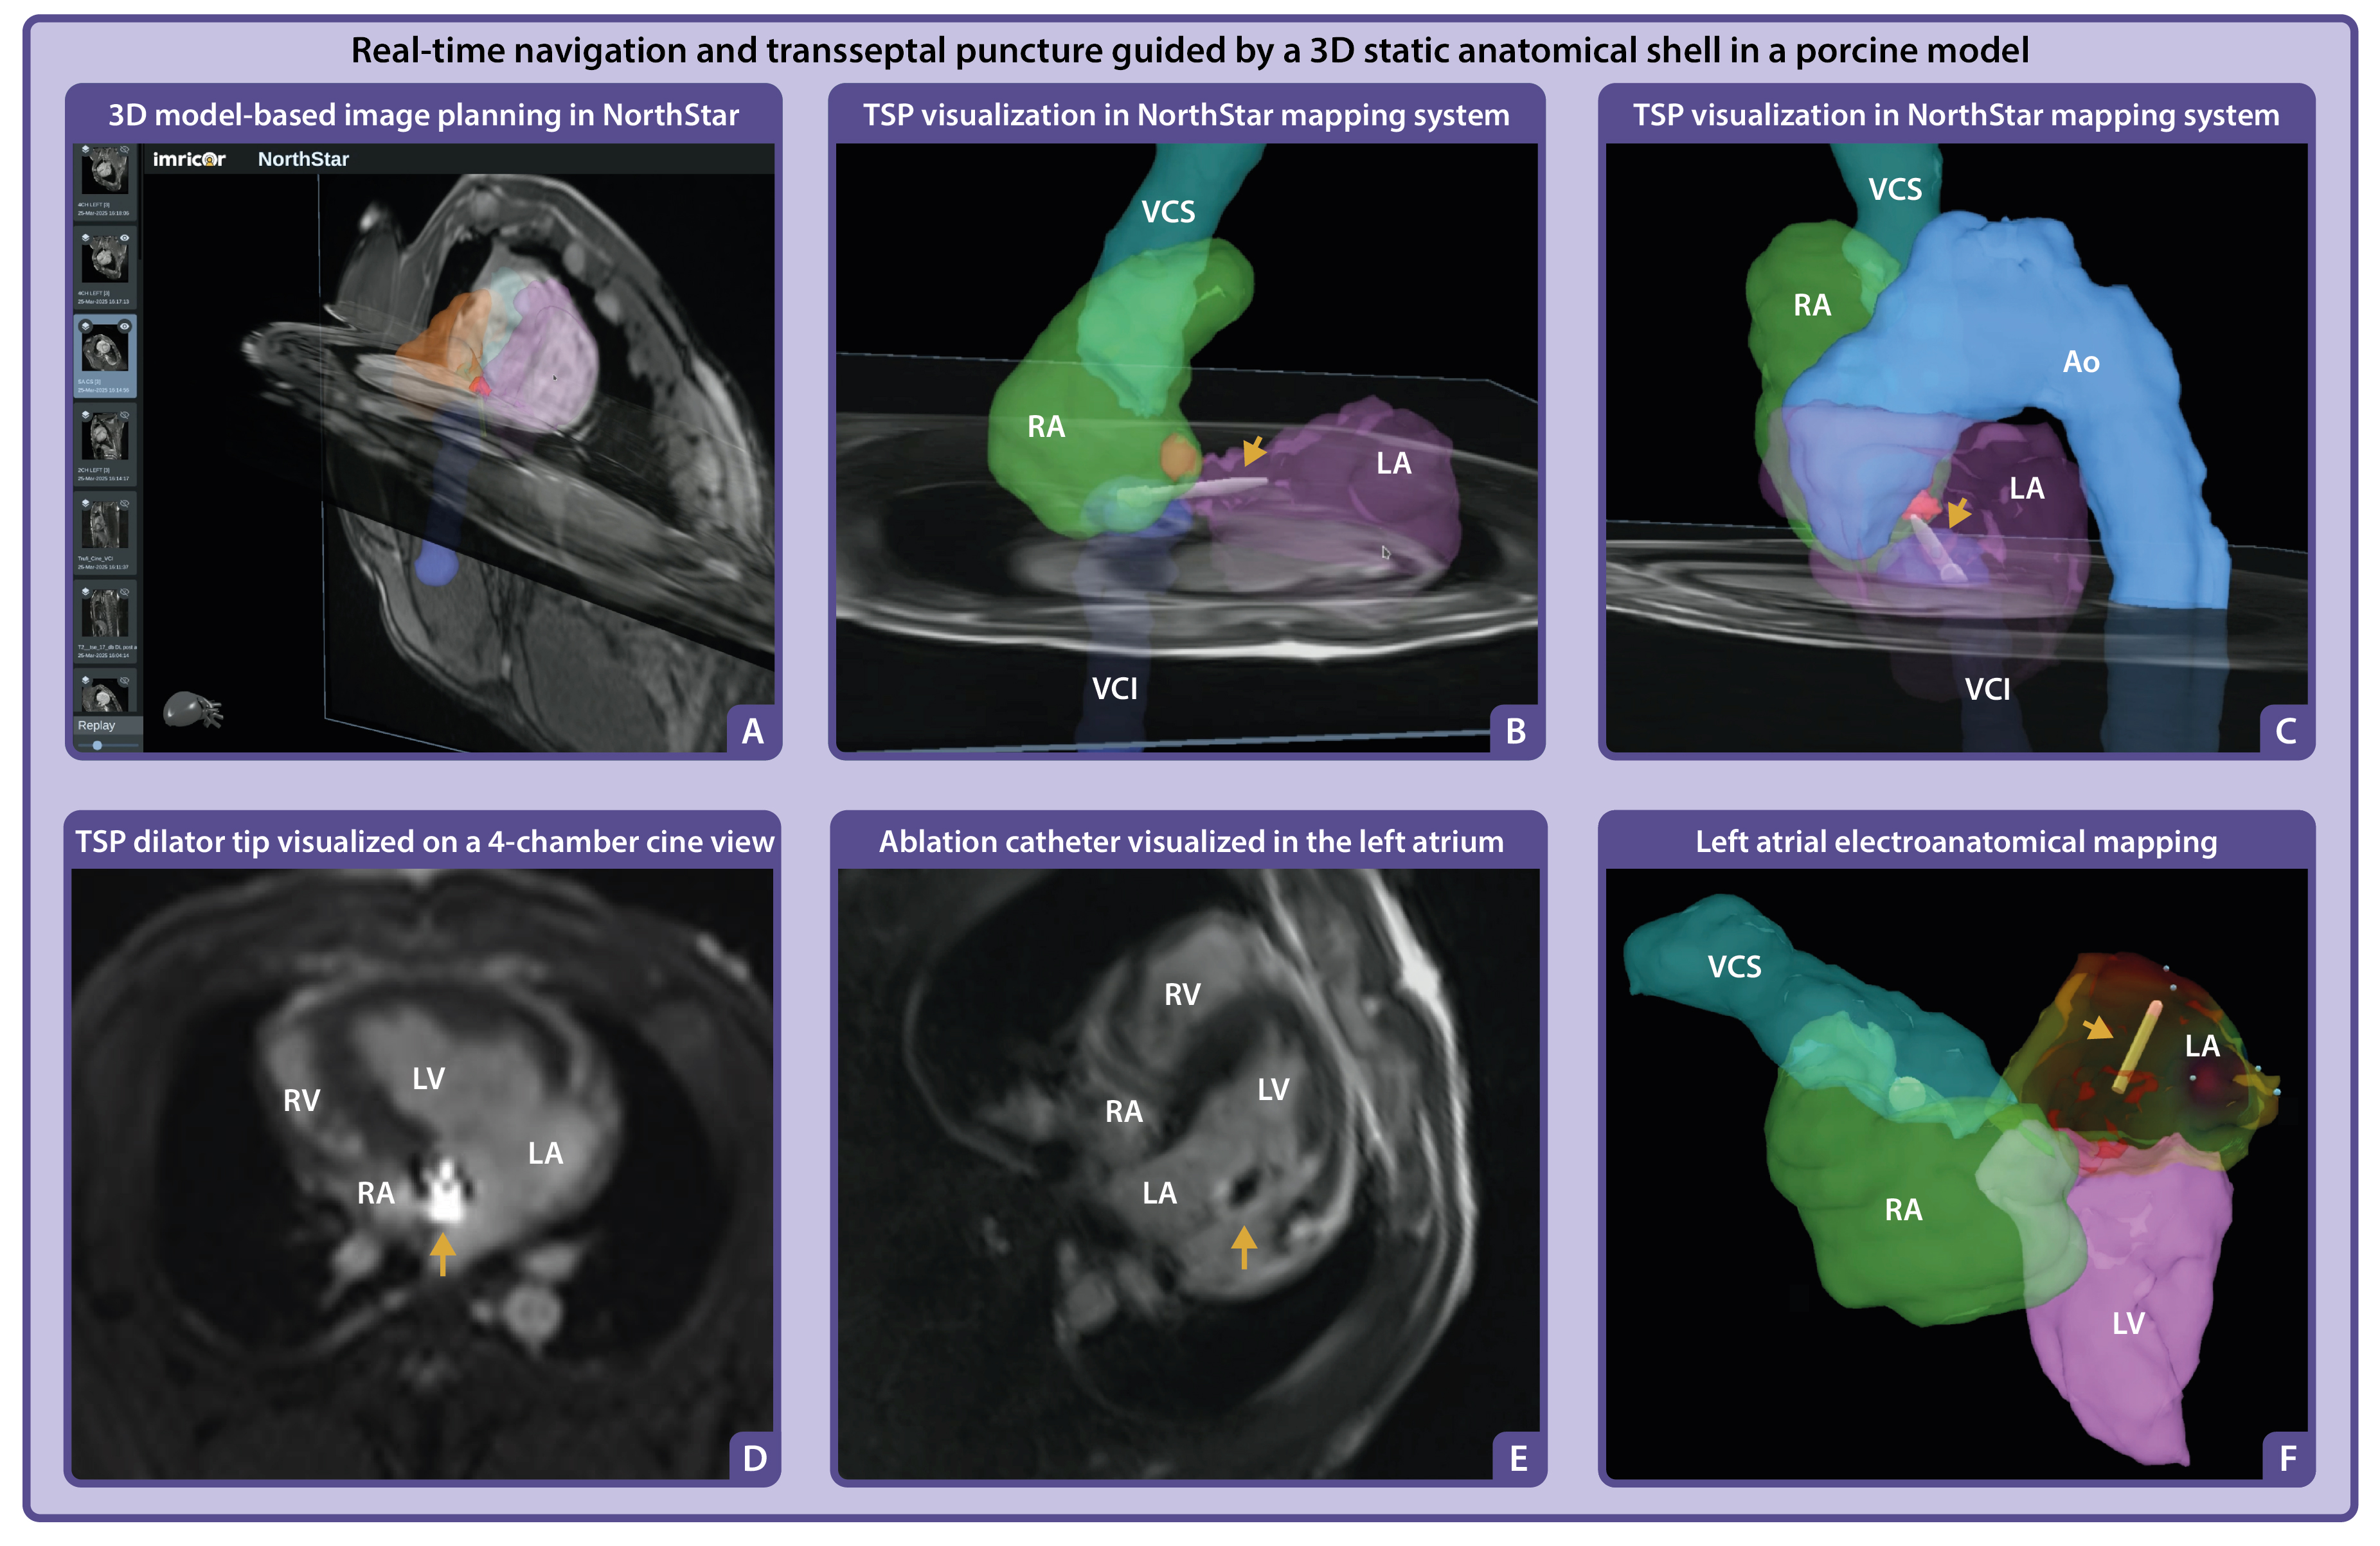

Methods: Real-time MR-guided TSP was performed in a porcine model using an investigational MR-compatible TSP set (Imricor Medical Systems, USA) consisting of a non-ferromagnetic sheath, dilator, and needle. Venous access was obtained via the femoral vein, and devices were advanced through the inferior vena cava into the right atrium. Real-time balanced SSFP imaging in three key planes: adjusted right ventricular (RV) two-chamber, basal short-axis, and four-chamber views, was used to guide catheter positioning and septal engagement. A high-resolution 3D dataset was acquired to generate a segmented anatomical shell of the heart, which was imported into the NorthStar 3D navigation system. Active tracking of the dilator was achieved via integrated miniature receiver coils, enabling continuous localization within the 3D roadmap.

Results: Transseptal access to the left atrium was successfully achieved under real-time MRI guidance. Dedicated imaging planes allowed clear visualization of device movement, septal tenting, and avoidance of critical adjacent structures such as the aortic root and posterior atrial wall. The NorthStar system provided spatial orientation by integrating real-time catheter tracking with the static 3D shell. Following septal puncture, an MR-compatible ablation catheter was advanced into the left atrium and local activation times were recorded to generate a left atrial activation map. Despite passive guidewire limitations, the integrated imaging and navigation approach enabled safe and controlled execution of the TSP.

A. Navigation of the MR-compatible TSP set within a 3D static anatomical shell imported into the NorthStar Mapping System, supplemented with adjustable 2D image planes to provide additional spatial orientation and visualization of cardiac motion. B–C. The TSP set was navigated to the foramen ovale (highlighted in red segmentation), with positioning verified across multiple image planes to ensure accurate alignment for septal puncture. The dilator tip is projected onto the shell (yellow arrow). D. Positioning of the dilator tip confirmed on a real-time 4-chamber cine image using active catheter imaging, where the tip appears as a bright signal focus (yellow arrow). E. Following TSP and advancement of the ablation catheter into the left atrium, a 4-chamber cine image confirmed its position, visualized by the catheter tip artifact (yellow arrow) in the left atrium. F. The ablation catheter (yellow arrow) projected in the NorthStar Mapping System during activation mapping of the left atrium.

A. Navigation of the MR-compatible TSP set within a 3D static anatomical shell imported into the NorthStar Mapping System, supplemented with adjustable 2D image planes to provide additional spatial orientation and visualization of cardiac motion. B–C. The TSP set was navigated to the foramen ovale (highlighted in red segmentation), with positioning verified across multiple image planes to ensure accurate alignment for septal puncture. The dilator tip is projected onto the shell (yellow arrow). D. Positioning of the dilator tip confirmed on a real-time 4-chamber cine image using active catheter imaging, where the tip appears as a bright signal focus (yellow arrow). E. Following TSP and advancement of the ablation catheter into the left atrium, a 4-chamber cine image confirmed its position, visualized by the catheter tip artifact (yellow arrow) in the left atrium. F. The ablation catheter (yellow arrow) projected in the NorthStar Mapping System during activation mapping of the left atrium.

Methods: Real-time MR-guided TSP was performed in a porcine model using an investigational MR-compatible TSP set (Imricor Medical Systems, USA) consisting of a non-ferromagnetic sheath, dilator, and needle. Venous access was obtained via the femoral vein, and devices were advanced through the inferior vena cava into the right atrium. Real-time balanced SSFP imaging in three key planes: adjusted right ventricular (RV) two-chamber, basal short-axis, and four-chamber views, was used to guide catheter positioning and septal engagement. A high-resolution 3D dataset was acquired to generate a segmented anatomical shell of the heart, which was imported into the NorthStar 3D navigation system. Active tracking of the dilator was achieved via integrated miniature receiver coils, enabling continuous localization within the 3D roadmap.

Results: Transseptal access to the left atrium was successfully achieved under real-time MRI guidance. Dedicated imaging planes allowed clear visualization of device movement, septal tenting, and avoidance of critical adjacent structures such as the aortic root and posterior atrial wall. The NorthStar system provided spatial orientation by integrating real-time catheter tracking with the static 3D shell. Following septal puncture, an MR-compatible ablation catheter was advanced into the left atrium and local activation times were recorded to generate a left atrial activation map. Despite passive guidewire limitations, the integrated imaging and navigation approach enabled safe and controlled execution of the TSP.

Right ventricular two-chamber view (comparable fluoroscopy orientation: right anterior oblique), basal short axis view (comparable fluoroscopy orientation: left anterior oblique), and four-chamber view. The yellow arrow indicates the foramen ovale. A. Navigation of the MR-compatible TSP set within a 3D static anatomical shell imported into the NorthStar Mapping System, supplemented with adjustable 2D image planes to provide additional spatial orientation and visualization of cardiac motion. B–C. The TSP set was navigated to the foramen ovale (highlighted in red segmentation), with positioning verified across multiple image planes to ensure accurate alignment for septal puncture. The dilator tip is projected onto the shell (yellow arrow). D. Positioning of the dilator tip confirmed on a real-time 4-chamber cine image using active catheter imaging, where the tip appears as a bright signal focus (yellow arrow). E. Following TSP and advancement of the ablation catheter into the left atrium, a 4-chamber cine image confirmed its position, visualized by the catheter tip artifact (yellow arrow) in the left atrium. F. The ablation catheter (yellow arrow) projected in the NorthStar Mapping System during activation mapping of the left atrium.

A. Navigation of the MR-compatible TSP set within a 3D static anatomical shell imported into the NorthStar Mapping System, supplemented with adjustable 2D image planes to provide additional spatial orientation and visualization of cardiac motion. B–C. The TSP set was navigated to the foramen ovale (highlighted in red segmentation), with positioning verified across multiple image planes to ensure accurate alignment for septal puncture. The dilator tip is projected onto the shell (yellow arrow). D. Positioning of the dilator tip confirmed on a real-time 4-chamber cine image using active catheter imaging, where the tip appears as a bright signal focus (yellow arrow). E. Following TSP and advancement of the ablation catheter into the left atrium, a 4-chamber cine image confirmed its position, visualized by the catheter tip artifact (yellow arrow) in the left atrium. F. The ablation catheter (yellow arrow) projected in the NorthStar Mapping System during activation mapping of the left atrium.